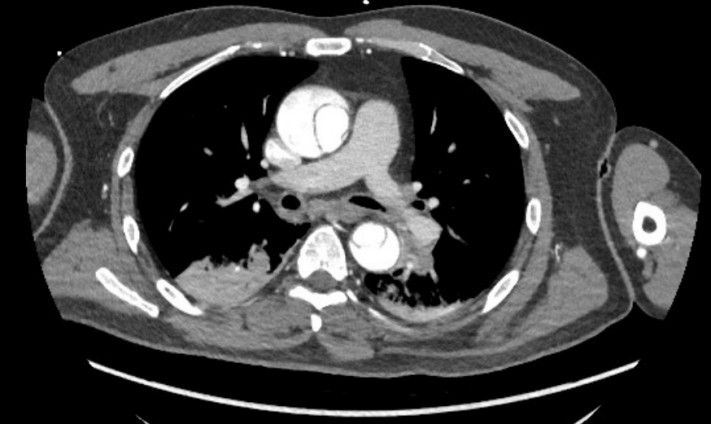

就在数小时前,这位老东谈主在家中剧烈胸痛,伴胸闷、心悸、冒盗汗,随后出现左侧肢体乏力、意志迁延、话语不清。家属热切送医。当地病院的CTA查验着力令东谈主心头一千里:A型主动脉夹层!这是心血管疾病中最为不吉的急症之一,起病急、施展快、物化率极高,若不足时手术,48小时内物化率高达50%及以上。

△CTA教导主动脉夹层A型

更毒手的是,患者的A型主动脉夹层,这种夹层扯破不仅发生在胸腔的大血管内,还进取推广,累及了通往大脑的右侧颈动脉整段,导致右侧大脑半球出现分水岭脑梗死,脑灌输严重减低。